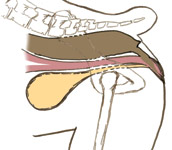

Foto 1: Un pug hembra de 8 semanas de edad con atresia tipo 1. Se inserta una sonda roma en el canal estenótico. Los conductos de los sacos anales son visibles.

La atresia anal consta de cuatro tipos de anomalías de severidad progresiva. El tipo I corresponde a la estenosis congénita anal sin ano imperforado (Foto 1). Las anomalías de tipo II y III constituyen un ano imperforado a una distancia <1,5 cm (tipo II) o > 1,5 cm (tipo III) de un saco ciego rectal (Foto 2). Las anomalías del Tipo IV son raras e involucran a un saco ciego rectal con desarrollo normal de la parte terminal del recto.